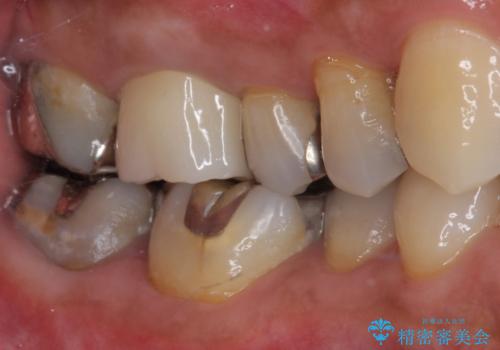

- 右上の小臼歯部に咬んだときに強い痛みを感じるとのことで来院された患者様です。

診査を行った結果、根管治療を行った後にオールセラミッククラウンにて補綴する治療計画となりました。

咬んだときの痛みに加えて夜間のズキズキする痛みもありましたが、1回目の根管治療実施後間もなく咬んだときの痛みがなくなったので、2回目に根管充填を行いました。